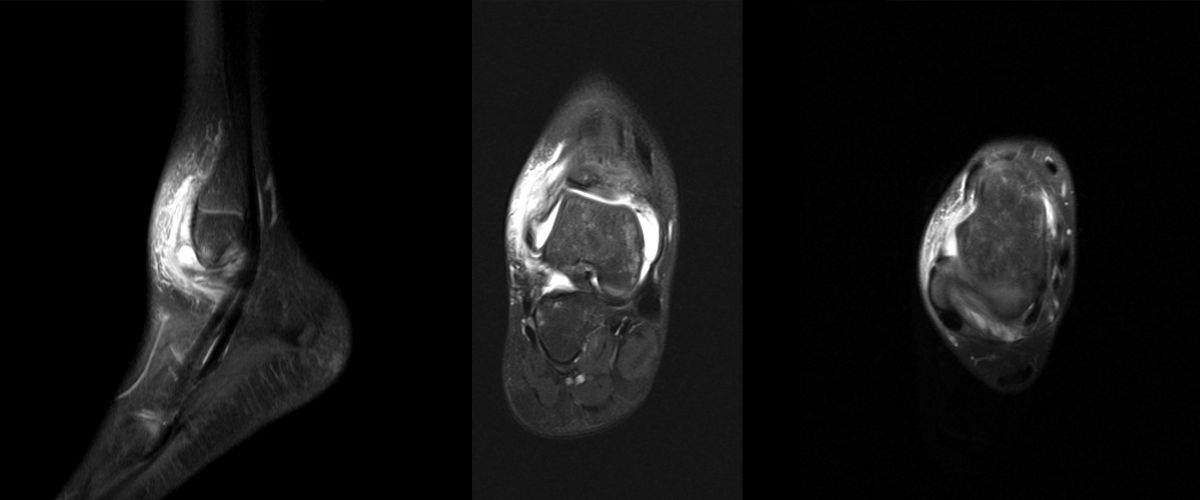

MRT

Die Kernspintomographie hat ihre Stärke in der Darstellung von Weichteilverletzungen. Insbesondere Verletzungen der Wachstumsfuge, des Periosts und der Bänder lassen sich gut visualisieren. Nachteilig ist die Untersuchungsdauer von 20-30 Minuten. Bleibt das Kind während dieser Zeit nicht ruhig liegen, kommt es zu Bewegungsartefakten, welche die Beurteilbarkeit der Bilder beeinträchtigen.

Os subfibulare

Multiple laminäre Ausrisse des fibularen Bandapparats aus der Fibulaspitze können zur Entwicklung eines Os subfibulare führen. Das Os subfibulare findet sich unterhalb der Fibulaspitze ventral der Peronealsehnen. Ohne Schmerzsymptomatik bzw. Aktivierung im MRT hat Das Os subfibulare keinen Krankheitswert. Ein mobiles Os subfibulare führt zu einer lokalen mechanischen Reizung teilweise in Verbindung mit einer Instabilität des Sprunggelenks. Im MRT zeigt sich eine Aktivierung des instabilen Areals. Bei anhaltenden Schmerzen besteht die Behandlung in einer operativen Entfernung des Knochens mit Refixation des Kapselbandapparats.

Osteochondrale Verletzungen

Osteochondrale Verletzungen können infolge eines Distorsionstraumas beobachtet werden (Taluskantenfraktur), teilweise lässt sich auch kein Trauma eruieren. Der es sich bei osteochondralen Verletzungen um keine Arthrose handelt, ist gerade bei Schmerzfreiheit ein defensives Vorgehen angezeigt. Bei offenen Wachstumsfugen kann eine osteochondrale Verletzung unter konservativer Therapie ausheilen.

Eine retrograde Anbohrung ist indiziert, wenn sich im MRT Verlauf eine zunehmende Sklerosierung im Randbereich der Läsion zeigt bei intakter Knorpeloberfläche.

Instabile Knorpelareale werden arthroskopisch entfernt in Verbindung mit einer Mikrofrakturierung der subchondralen Knochenlamelle.